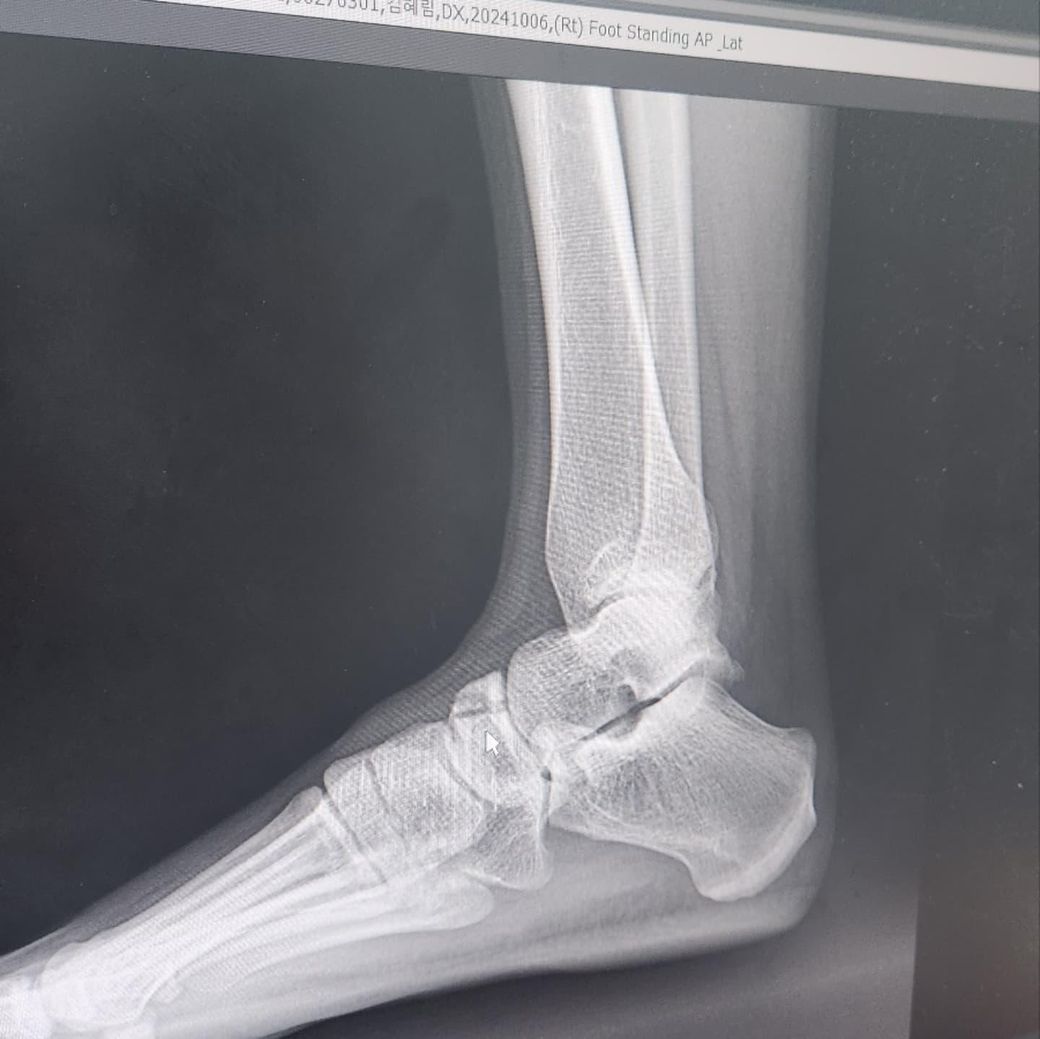

족부 주상골 골절 발바닥에 피 뭉쳐있는 느낌

비수술 통깁스 입니다 어제부터 발바닥에 엄청 따뜻한 피가 모여있는 느낌인데 지들끼리 모여있다가 발을 내리면 아래로 내려가요 혹시 피가 고여있는 걸까요? 안좋은 건가요...? 참고로 10월 6일에 골절됐습니다. 아래 엑스레이는 10월 6일 촬영 사진입니다.발바닥이 엄청 따뜻해요...열감이랑은 다른느낌으로...끈적한 액체가 들어있는 느낌

• 1번 째 사진

• 2번 째 사진